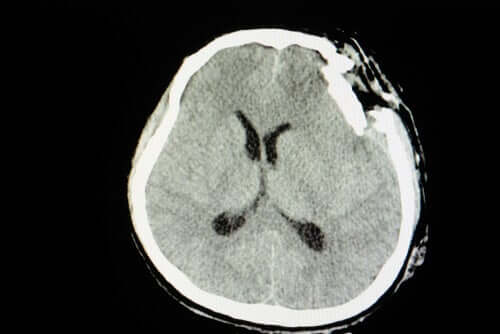

Un trauma cranico è un disturbo neurologico causato da un violento urto. Così come possiamo ferirci o fratturarci un braccio, potremmo danneggiare la base del sistema nervoso. L’unica differenza è che le conseguenze saranno molto più gravi.

Non è la stessa cosa avere un’infiammazione derivante da un colpo o una perdita di massa encefalica con una frattura esposta del cranio. Allo stesso modo, possiamo affermare che le conseguenze principali sono evidenti a livello cognitivo, di memoria e di personalità.